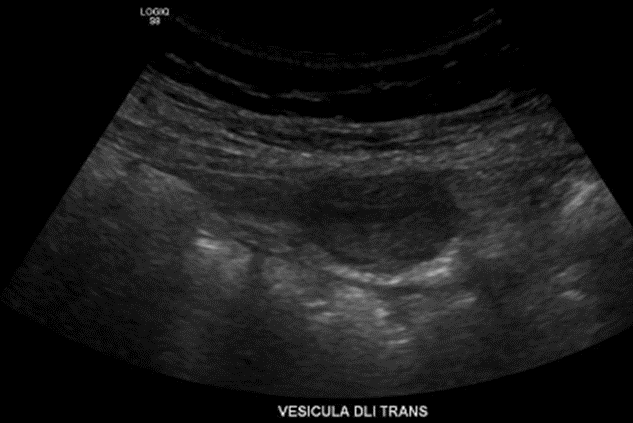

• En fondo vesicular se observa imagen sólida, no móvil al cambio de posición, ecogénica, irregular, con señal al doppler color y espectral, hallazgo que puede corresponder a proceso neoplásico, sugerente Ca vesicular.

Vesícula biliar normalmente distendida con masas hipoecogénicas, vascularizadas y bien definida en fondo vesicular, de aprox 43 mm. Se observa un cálculo en el interior vesicular de 34 mm.

Impresión diagnóstica: Tumor vesicular de aspecto neoplásico que requiere estudio complementario.

Colelitiasis